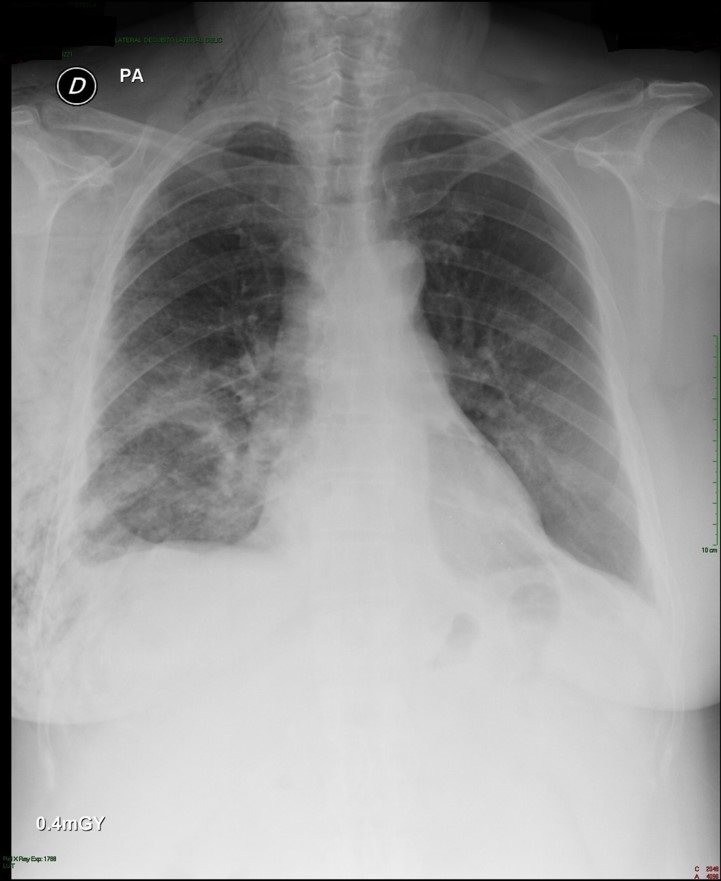

The current treatment algorithm, which often starts as several weeks of outpatient antibiotics, (usually initiated for treatment of community acquired pneumonia that develops into a parapneumonic effusion), that engenders an even longer period after subsequent follow up chest x-rays, then CT scan fail to show improvement.

A pneumonia in late September, becomes an effusion in October, then progresses to empyema as various strategies are attempted and fail.  One antibiotic is switched to another, a pigtail is placed in radiology (with partial results), then perhaps, a larger tube, and fibrinolytics.  Then, only then – is the thoracic surgery service consulted.